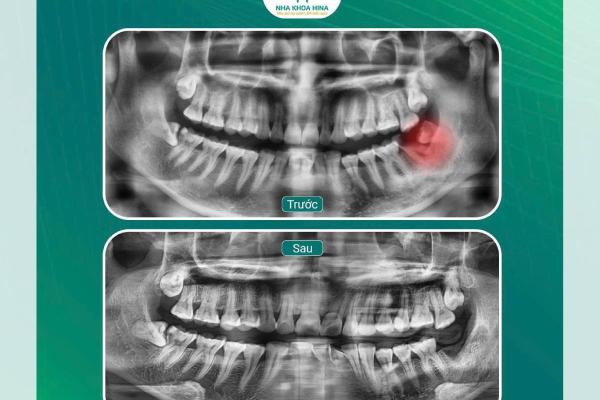

Nhổ răng khôn số r47, 48

Răng khôn số R47, R48 là hai răng mọc cuối cùng...